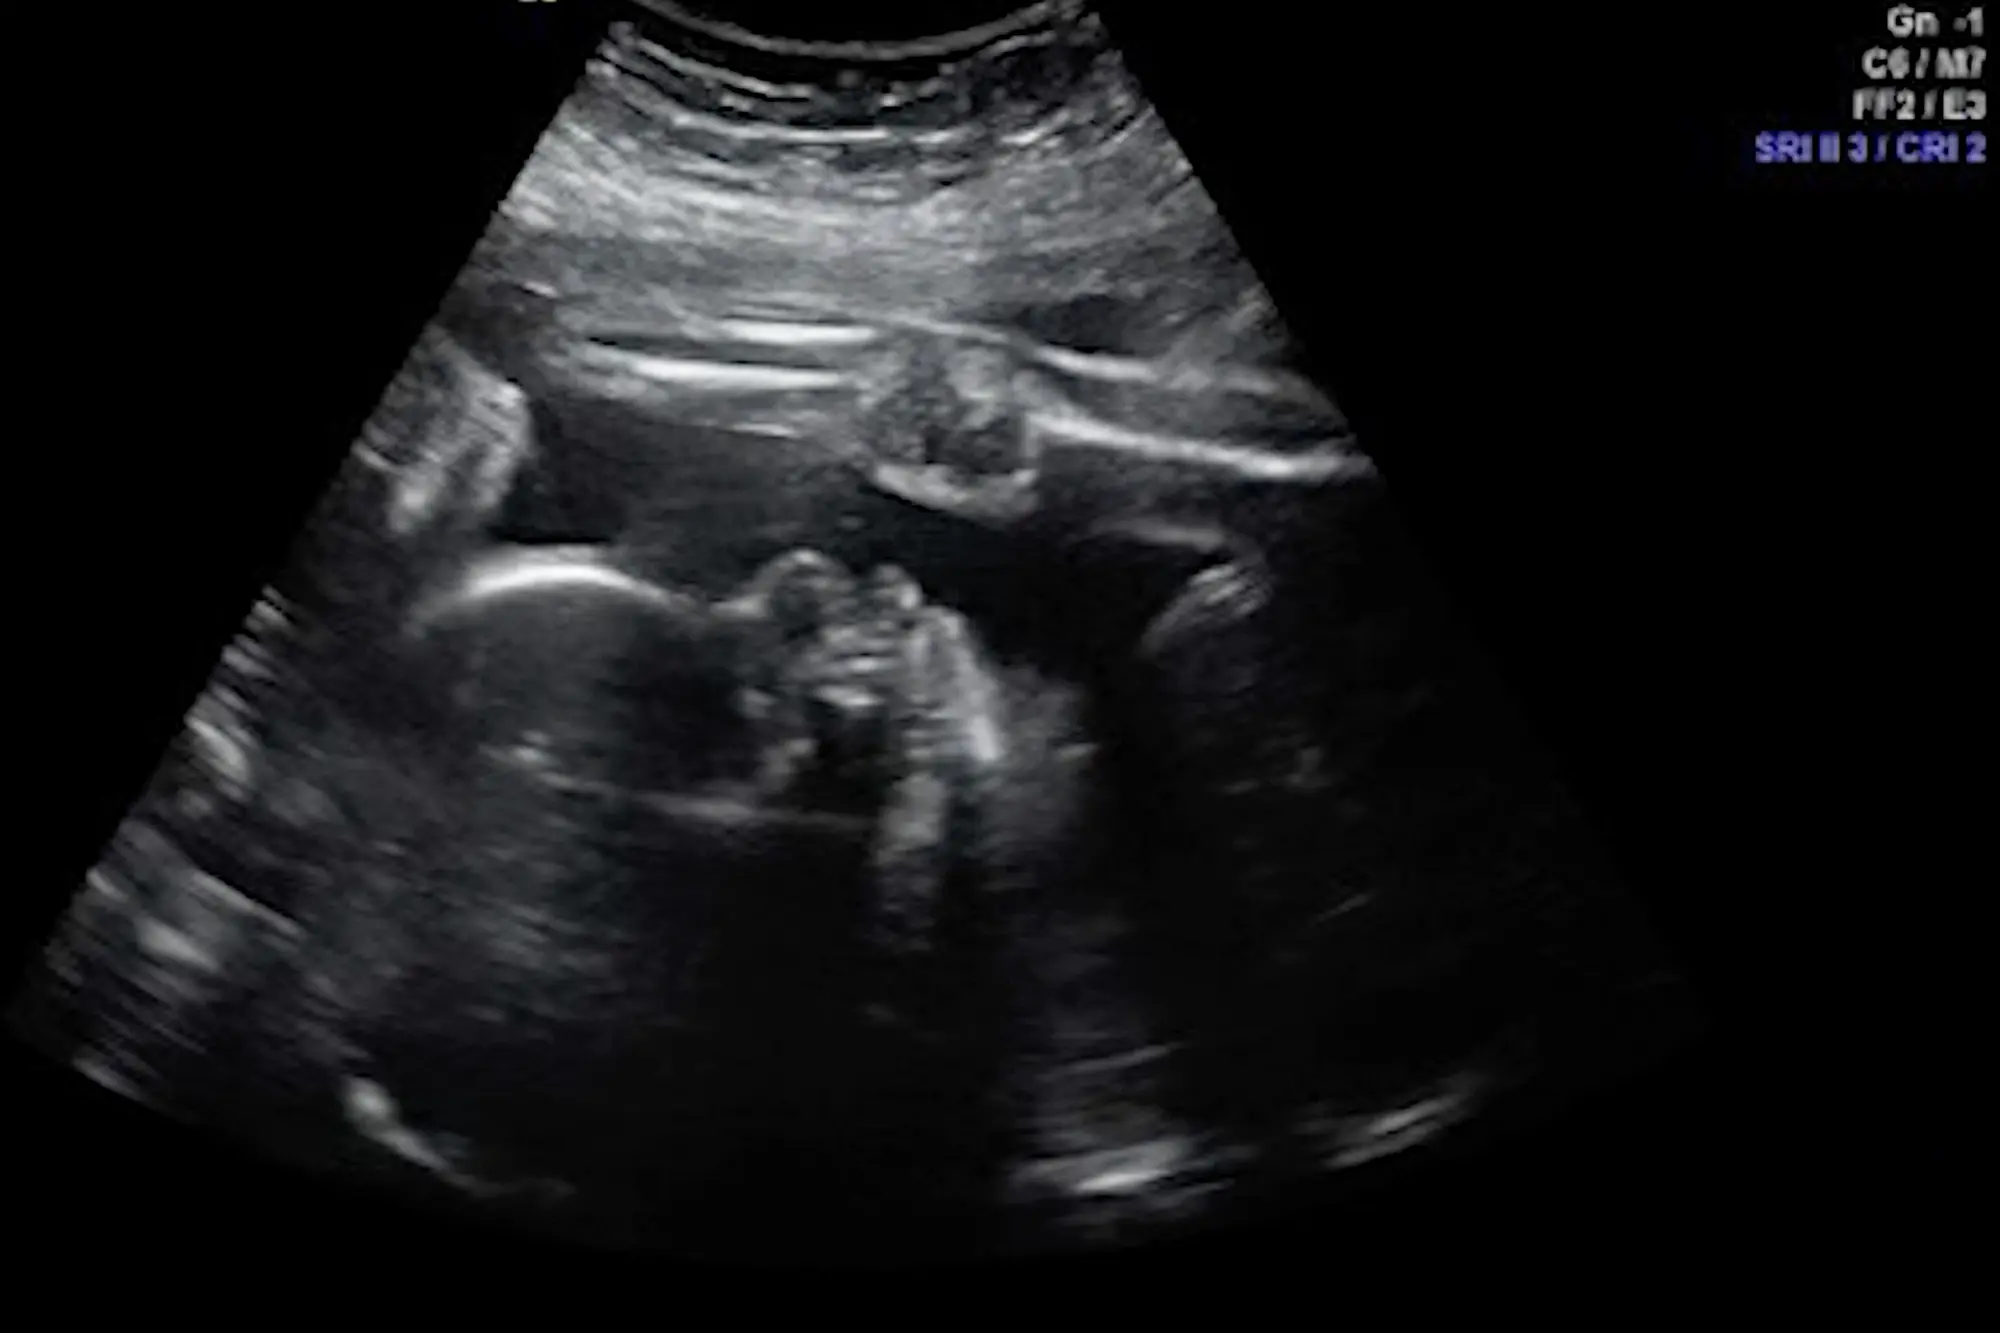

Une première dans l'histoire médicale. Si les opérations in utero sont assez peu fréquentes en règle générale, opérer le cerveau d’un fœtus dans l’utérus de sa mère relève de la prouesse médicale. C’est donc un cas unique qui s’est présenté à une équipe de chirurgiens du Massachusetts General Hospital et de l’hôpital pour enfants de Boston.

Ces médecins ont opéré un vaisseau sanguin malformé dans le cerveau d’un bébé se trouvant encore dans l’utérus de sa mère. Kenyatta et Derek Coleman attendent leur quatrième enfant, lorsque le couple originaire de l’État de Louisiane aux États-Unis apprend que leur bébé est atteint d’une malformation foetale rare : la malformation anévrismale de la veine de Galien (MAVG).

Dans ce genre de chirurgie, il y a en réalité deux patients : la mère et son bébé. Les médecins devaient s’assurer que le fœtus était dans la bonne position, avec sa tête contre l’abdomen de sa mère, pour faciliter l’opération.

Ils ont ensuite utilisé un cathéter dans la veine de Galien pour ralentir le flux sanguin et réduire la pression, grâce à des minuscules bobines métalliques injectées dans la varice. “Une fois que le fœtus est en position optimale, il reçoit une petite injection de médicament pour qu'il ne bouge pas et une seconde pour soulager la douleur", explique le Dr Louise Wilkins-Haug, directrice de division de médecine foeto-martenelle et de génétique reproductive de l’hôpital de Boston, qui a participé à l’opération.